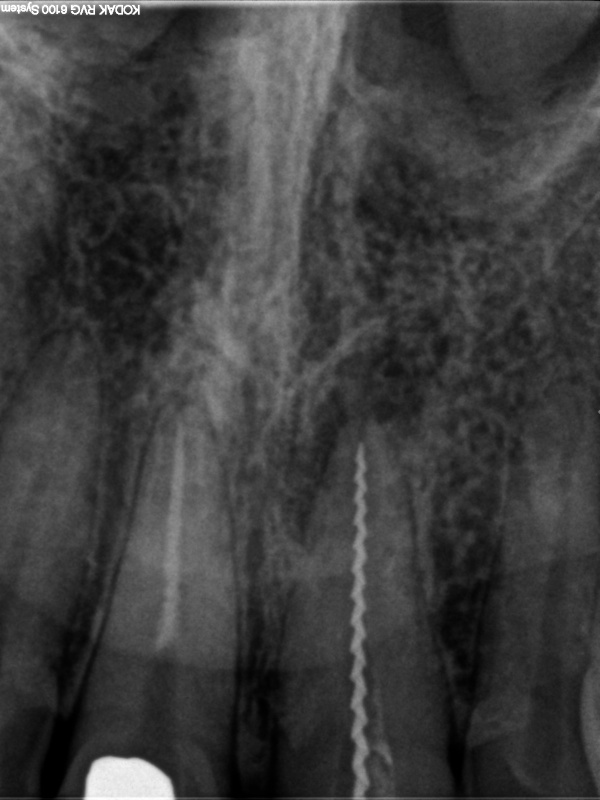

und wieder ein Recall

Ausgangssituation